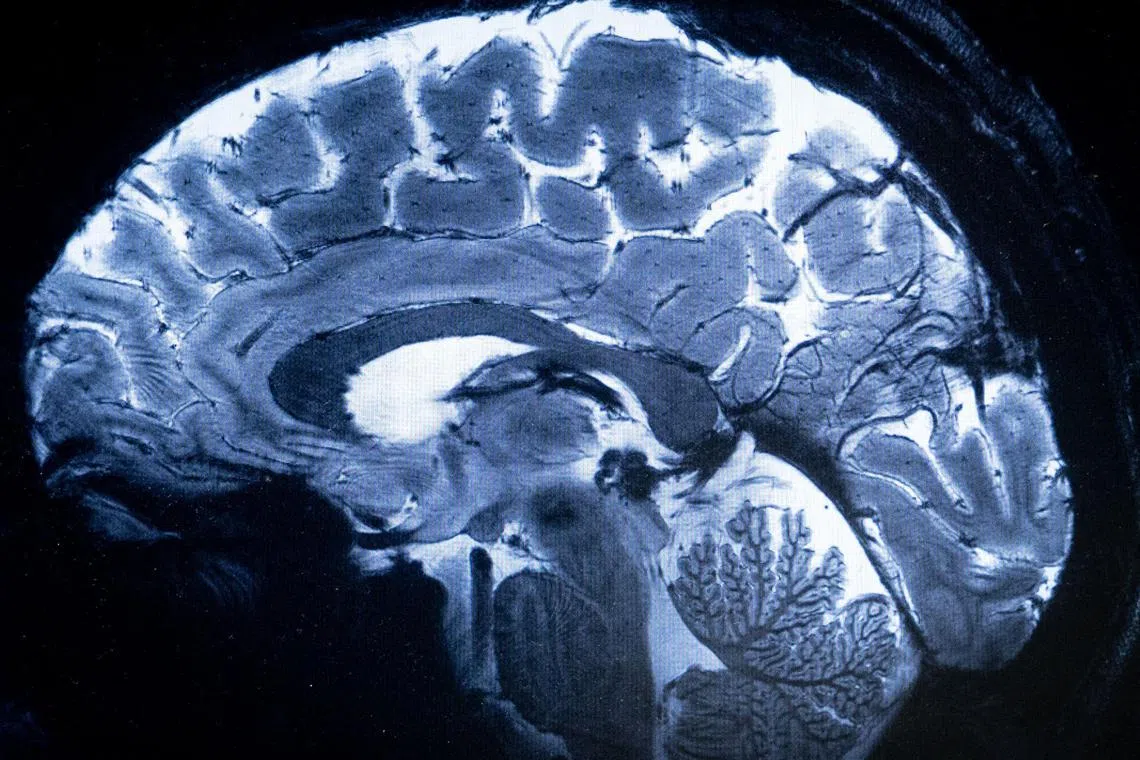

SACLAY, France – The world’s most powerful MRI scanner has delivered its first images of human brains, reaching a new level of precision that is hoped to shed more light on our mysterious minds – and the illnesses that haunt them.

“We have seen a level of precision never reached before at CEA,” said Dr Alexandre Vignaud, a physicist working on the project.

This power allows the machine to scan images with 10 times more precision than the MRIs commonly used in hospitals, whose power does not normally exceed three teslas.

On a computer screen, Dr Vignaud compared images taken by this mighty scanner, dubbed Iseult, with those from a normal MRI.

“With this machine, we can see the tiny vessels which feed the cerebral cortex, or details of the cerebellum, which were almost invisible until now,” he said.